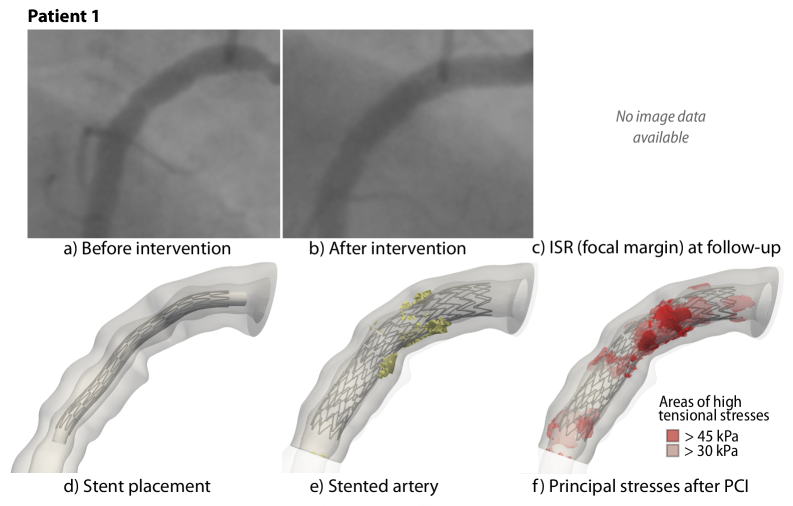

Appendix D Stent placement and correspondence to angiography data

In the following, we compare the simulation results of Patient 1, 2, 3, and 4 to the angiography imaging data, see Fig. 11, 12, 13, and 14, respectively. We select single frames during the diastole from the respective angiography data. For each patient, Subfigures a) and d) show the configuration before the intervention. Subfigures b) and e) show the angiography image after the intervention and the simulated stented artery. Subfigures c) and f) compare the follow-up angiography with the maximum stresses after the intervention.

Refer to caption

Figure 11: Stent placement and corresponding angiography data for Patient 1

Figure 15: First principal stress values in selected cross-sections during and after PCI; Patient 1. The plaque morphology is shown in the CCTA cross-sections and in the model. The stent cross-section is shown as black dots. Ca: Calcification.

Patient 1 shows the following plaque characteristics in the cross-sections: one-sided block calcification (Slice B), small block calcification with scattered calcified particles (Slice C), opposing calcifications (Slice D), see Fig. 15. During maximum balloon inflation (Fig. 15, third row), stress peaks can mainly be observed near the calcifications. High stresses occur in the media and adventitia, especially in the thin-walled area next to the larger calcifications in Slice D. After PCI, the stress values are reduced; however, the spatial distribution is similar to the maximum pressure state.